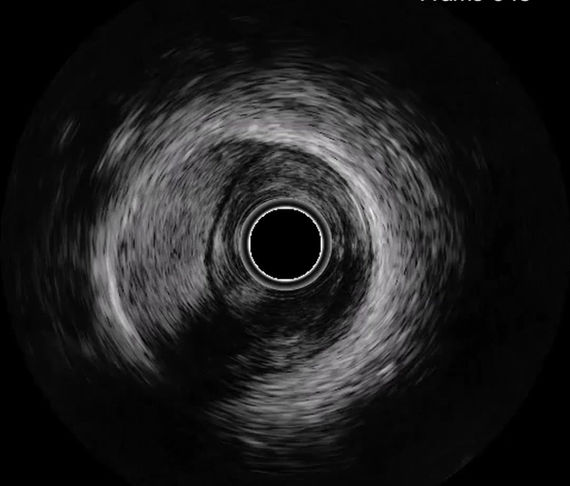

Plaque rupture

Dissection

Thrombus

Haematoma

False lumen

Tissue prolapse